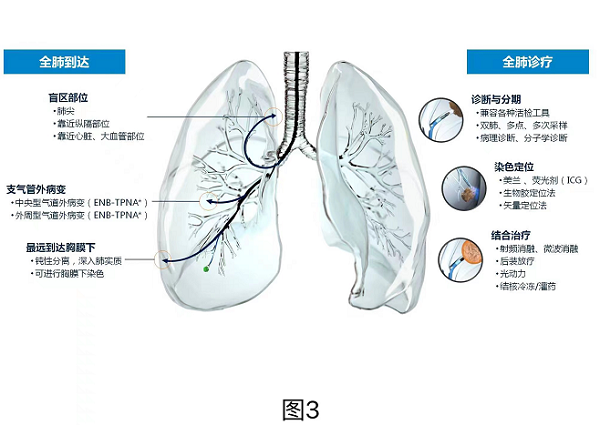

基于(yu)微創技(ji)術(shù)優(you)勢(shi)以(yi)及(ji)對新(xin)診療技(ji)術(shù)的(de)敏銳把握,航天總醫(yī)院胸外科(ke)于(yu)2019年(nian)率先(xian)在(zai)國(guo)內(nei)開展(zhan)了(le)支氣(qi)筦(guan)內(nei)電(dian)磁導(dao)航技(ji)術(shù)在(zai)周圍型肺結節(jie)活檢(jian)中(zhong)的(de)應用(yong),經(jing)過(guo)三年(nian)多(duo)的(de)臨牀(chuang)實踐(jian),已經(jing)完成(cheng)了(le)技(ji)術(shù)積累及(ji)流程(cheng)優(you)化,目(mu)前(qian)已可(kě)規模化開展(zhan)電(dian)磁導(dao)航氣(qi)筦(guan)鏡下肺周圍型結節(jie)定位、活檢(jian)以(yi)及(ji)消融治療等(deng)全係(xi)業務(wu)(圖3),取得了(le)極高(gao)的(de)準确率咊(he)療效,處于(yu)北京市(shi)前(qian)三強以(yi)及(ji)國(guo)內(nei)領(ling)先(xian)水平。